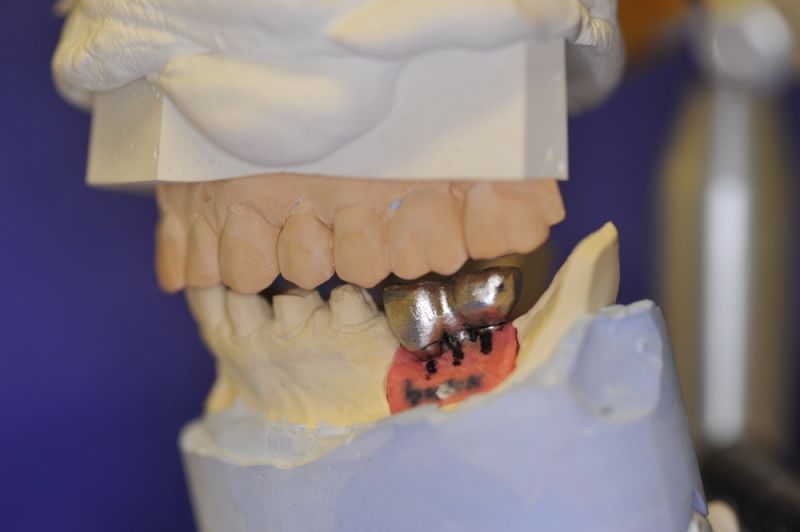

Nun stellte sich heraus, dass der Abstand zwischen den Implantaten sehr gering war, weil die Einschubrichtungen der Aufbauten sich zum Teil gegenseitig im Wege standen. Konfektionierte Teile mussten individuell umgeschliffen werden, dabei das Ziel, den Biss korrekt einzustellen nicht aus dem Auge zu verlieren.

Heute war nun Gerüsteinprobe, mit all den Problemen der Umsetzung zwischen Laborsituation und Mundsituation. Siehe Stichpunkt "Schnittstellenproblematik"! was bei Zähnen, auf Grund deren Eigenbeweglichkeit im Kieferkochen kein Problem wäre, ist bei drei unbeweglichen Implantaten ein Riesenproblem. Darüber spricht nur in aller Regel Niemand! Es musste viel fein nachgearbeitet werden.

4 Stunden haben wir heute Temporäre Aufbauten und provisorische Kronen entfernt. Definitive Aufbauten im Munde eingeschraubt. Eine erneute Bissregistrierung durchgeführt und die Arbeit neu artikuliert. Neue Provisorien mussten auch wieder hergestellt werden.

Eine Arbeit, bei der der Einsatz an Arbeitszeit überproportional hoch ist, aber mit weniger das gewünschte Ergebnis nicht zu erreichen sein wird. Letzte umfangreiche Besprechungen mit der Zahntechnikermeisterin, bevor es jetzt an die endgültige Herstellung der beiden Rekonstruktionsblöcke geht.